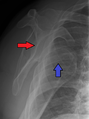

النقطة المضيئة تشير لخلع الكتف الخلفي على الجهة اليسرى. على اليمين، نفس الكتف بعد إجراء عملية الرد.

خلع الكتف الخلفي من الحالات الشائعة، وعادة ما يحدث بسبب انقباض العضلات بسبب صدمة كهربائية أو التشنج.[5] وقد يحدث نتيجة عدم توازن العضلاات المحيطة بالكتف. عادة ما يحمل المريض ذراعه بصورة دائرية إلى الداخل، كما تضعف العضلات المحيطة بالكتف مع حالة إصابة واضحة في النتوء الغرابي.

قد يحدث الخلع الخلفي لأسباب غير معروفة، وخاصة بين كبار السن[11] وفي حالات الصدمة الغير واعية.[12] في دراسة لمجموعة من 40 حالة، لوحظ أن الفترة بين الإصابة والتشخيص تصل إلى عام.[13]